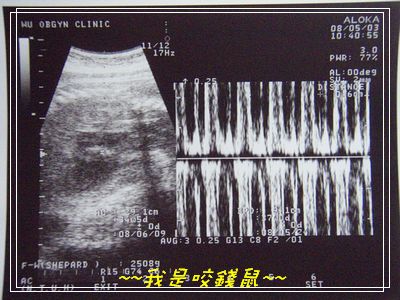

是ㄉ~~我也看不懂ㄉ超音波...

左邊照啥忘記啦~~右邊是咬錢鼠健康的心跳~~~

咬錢鼠依舊乖乖ㄉ...好好ㄉ...

目前他老媽我已經有很努力的散步走樓梯了..

希望這星期咬錢鼠就可以出來啦~~~